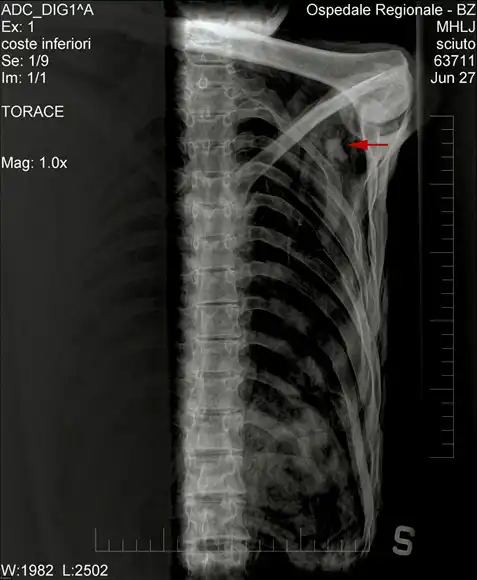

Красная стрелка указывает на то место, где тело Эци было найдено двумя немецкими туристами из Нюрнберга в 1991 году на высоте 3 200 метров. При Эци были найдены каменные орудия и артефакты эпохи неолита.

Рентген плеча «ледяного человека», наконечник стрелы отмечен красной стрелкой.